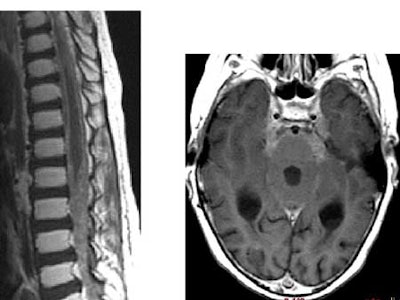

The Duke team sought to answer these questions by retrospectively reviewing the clinical records and imaging studies of 8 patients with TRB over 15 years. They looked for the presence of leptomeningeal tumor, the time of discovery of an intracranial mass, and the interval from discovery of intraspinal leptomeningeal disease. All 8 patients had cranial MR imaging, and 6 had spinal MR imaging using standard protocols.

Over the course of the study, six patients developed intracranial metastases as seen on MR imaging. Five of the patients developed intraspinal metastases, with four seen on MR, and one diagnosed by lumbar puncture, Provenzale said.

The time from detection of the primary intracranial mass and discovery of the intracranial leptomeningeal disease ranged from 7-26 months (mean, 13 months). Most were diagnosed within a year, however. The mean interval to discovery of intraspinal metastases was 9 months, with a range of 0-26 months.

A discernible progression pattern was seen in about half of the patients, who were diagnosed and treated for intracranial disease with some combination of chemotherapy, radiation, and surgery, Provenzale said. Following treatment, the primary intracranial tumor shrank, and there was a period of quiescence lasting from 1-4 years, followed by rapid development of intracranial and intraspinal leptomeningeal metastases.

"At some point in their therapy, many of our cases had little or no residual pineal tumor at the time of discovery of intracranial or intraspinal tumor spread, so if you're looking to see where disease is going to spread in these patients, it's equally important to look at the leptomeningeal spaces as it is to look at the site of the intracranial mass, whether it be pineal or suprasellar," Provenzale said.

Finally, because spinal metastases were present in some cases at the time of discovery of an intracranial mass, Provenzale recommended that spinal imaging be performed at the time of diagnosis of the primary tumor.

"Our protocol based on this data is to perform brain and spine MR imaging at the time of diagnosis of the intracranial tumor, and then at two-month intervals in the first year, four-month intervals in the second year, and at six-month intervals thereafter.... This seems to be a very aggressive neoplasm," he said.